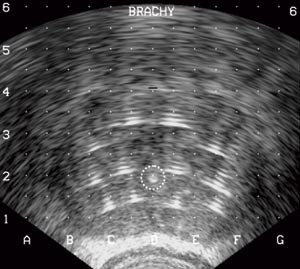

Til visuell fremstilling av prostata benyttes Bruel & Kjærs ultralydapparat Falcon 2101 med sonotrode B-K 8658 S 7,5 MHz. Sonotroden monteres på et eget stativ, en såkalt brakystand. Nær sonotroden har brakystanden et templat eller gjennomhullet stålplate. Hullene i platen vises på ultralydskjermen som et gitter. Dette gjør det mulig å føre nålene i ønsket posisjon inn i prostata (fig 2).

Prostata fremstilles i begge plan på ultralyd, og man bestemmer hvor mange nåler som skal benyttes. Nålene settes i ca. 7 mm avstand fra prostatakapselen og med inntil 10 mm innbyrdes avstand (1). Hver nåls posisjon kontrolleres i et transverselt (fig 3) og longitudinelt plan. Termosensorer plasseres i begge kjertelhalvdeler og utenfor fascien mellom prostata og rectum. Varmenåler settes i rectumveggen og ev. ved den nevrovaskulære bunt for å redusere faren for ereksjonssvikt (3). Når nålene er plassert, gjøres fiberoptisk cystoskopi for å kontrollere at ingen av dem perforerer urethra. Så legges varmekateteret inn.